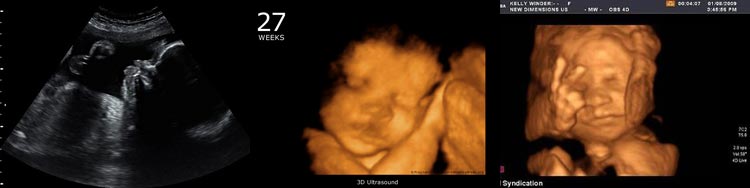

На 27-й неделе беременности ваш малыш по размеру сопоставим с капустой, достигая почти 37 сантиметров в длину и весит около 1250 граммов. Это почти в два раза больше его веса по сравнению с прошлой неделей! Если вы сделаете ультразвуковое исследование, то сможете увидеть, как он удобно устроился в матке.

| Слух: Слух хорошо развит, малыш различает голоса родителей, реагирует на музыку и громкие звуки. | Эмоции: Настроение может быть переменчивым из-за гормональных изменений. Возможны тревога и волнение перед родами. | УЗИ: На УЗИ можно увидеть, как малыш сосет пальчик, зевает, открывает и закрывает глазки. |